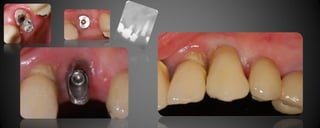

Prótesis Implanto Asistida

Las prótesis implanto asistidas, son restauraciones que utilizan los implantes

para retenerse y/o apoyarse. Los implantes sirven para reemplazar la raíz

del diente dentro del hueso, luego se realizará la restauración necesarias

(coronas, puentes, prótesis parciales o totales)

Prótesis Implanto Asistida Lasprótesis implanto asistidas, son restauraciones que utilizan los implantes para retenerse y/o apoyarse. Los implantes sirven para reemplazar la raíz del diente dentro del hueso, luego se realizará la restauración necesarias (coronas, puentes, prótesis parciales o totales)